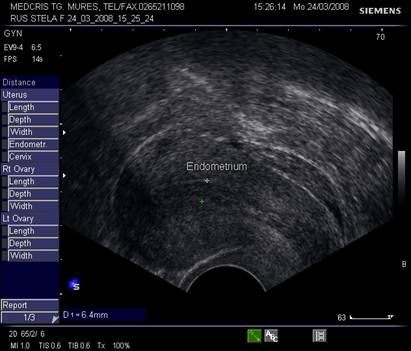

Endometrul - grosimea sa este apreciata in sectiune longitudinala. Masurarea se va face de la interfata miometru - endometru la interfata identica, opusa, de pe peretele celalat uterin. Maxim acceptat normal este de 1,5 cm in perioada de premenopauza.[5] Postmenopauza in mod normal nu depaseste 5 mm, de obicei este atrofic si apare ca o imagine ecogena lineara. Daca apare o colectie anecogena postmenopauzala intrauterina, prin atrofie cervicala, aceasta colectie nu trebuie sa fie masurata la calculul grosimii endometriale.[2,6]

Fig. nr.361. Endometru in faza de secretie incipienta

Fig nr.362. Endometru in faza de secretie tardiva ( Ziua a XI a de ciclu menstrual ). Se remarca linia continua dintre cele doua ecostructuri endometriale de pe peretii uterini opusi .

Fig. nr.363. Endometru la inceput de secretie ( ziua a XV a de ciclu menstrual , postovulator). Se remarca pierderea discreta a interliniei endometriale in regiunea periferica, in timp ce regiunea cavitatii uterine centrale pastreaza linia ecogena

Fig. Nr.364.Endometru de faza secretorie medie, cu pierderea interliniei caracteristica fazei de proliferare